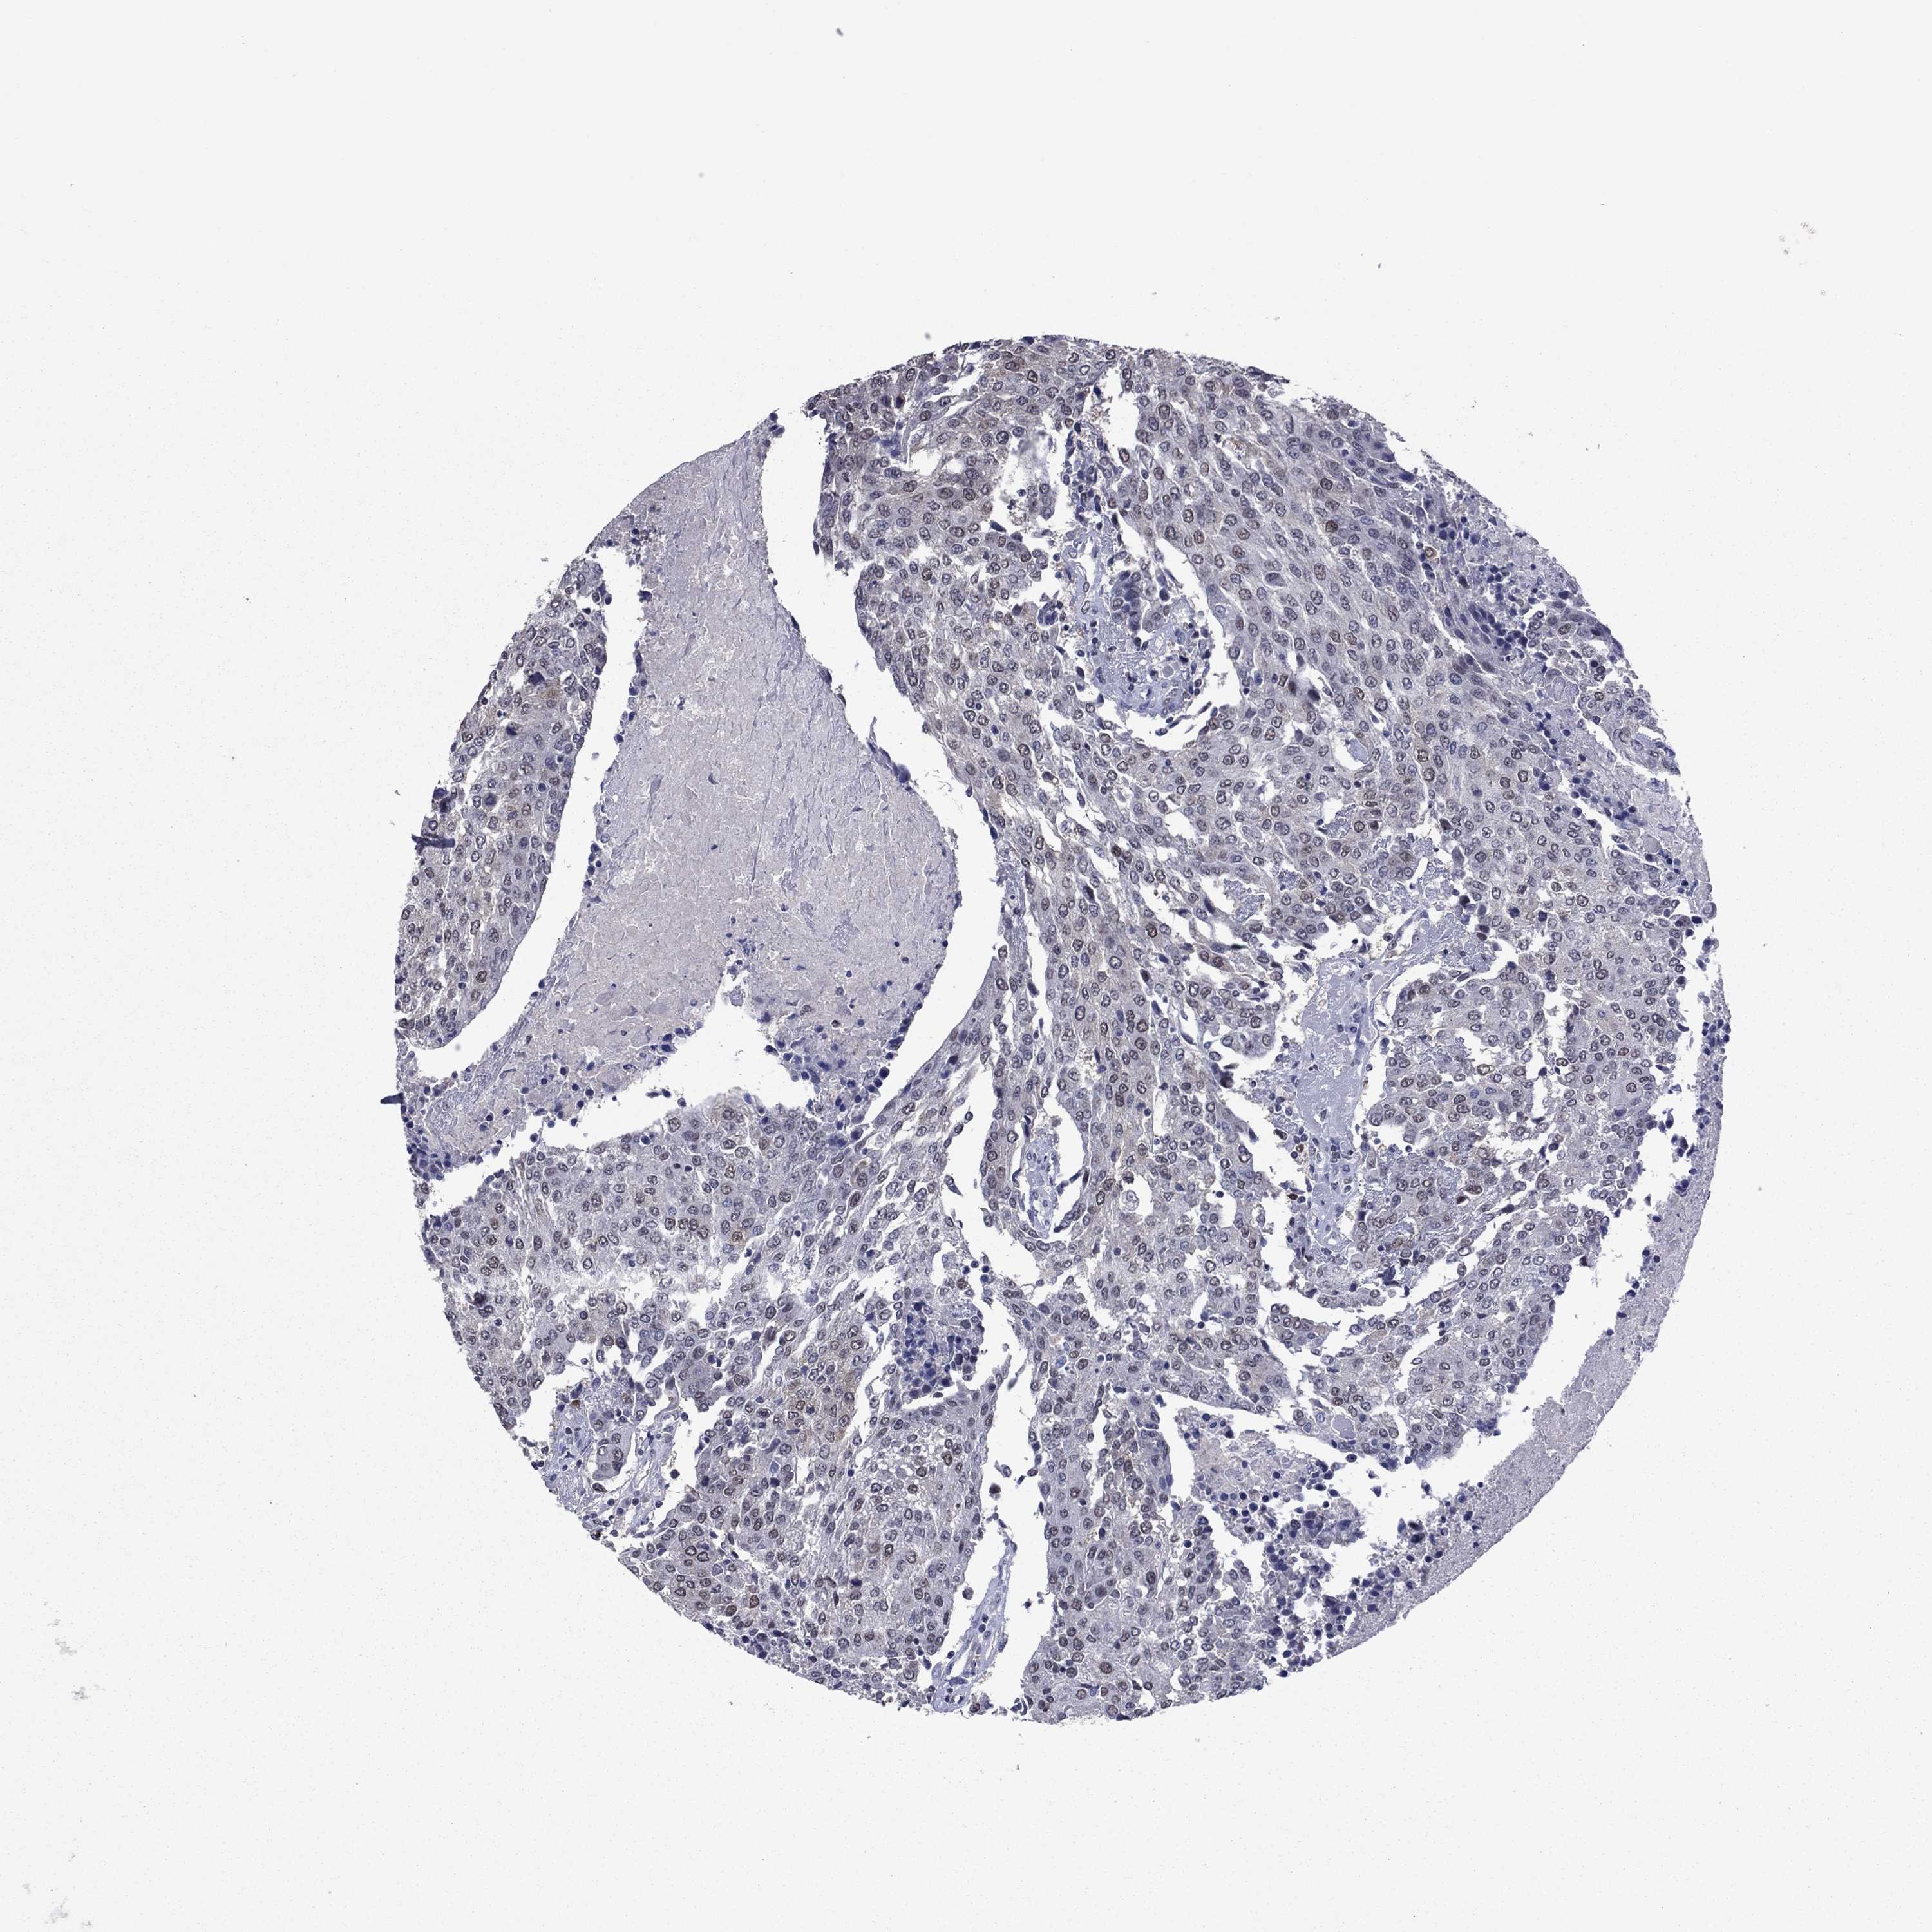

UROTHELIAL CANCER - Protein expressioni

A mouse-over function shows sample information and annotation data. Click on an image to view it in a full screen mode. Samples can be filtered based on level of antibody staining by selecting one or several of the following categories: high, medium, low and not detected. The assay and annotation is described here.

Antibody stainingi

Antibody staining in the annotated cell types in the current human tissue is reported as not detected, low, medium, or high, based on conventional immunohistochemistry profiling in selected tissues. This score is based on the combination of the staining intensity and fraction of stained cells.

Each image is clickable and will lead to virtual microscopy that enables deeper exploration of all samples and also displays staining intensity scores, fraction scores and subcellular localization as well as patient and tissue information for each sample.

Antibody HPA074922

Antibody CAB002784

Staining

High

Medium

Low

Not detected

Intensity

Strong

Moderate

Weak

Negative

Quantity

>75%

75%-25%

<25%

None

Location

Nuclear

Cytoplasmic/membranous

Cytoplasmic/membranous,nuclear

Urothelial carcinoma, High grade

Urothelial carcinoma, NOS

Urothelial carcinoma, Low grade

Adenocarcinoma, NOS